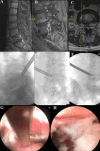

Results: Collectively, 19 cases described endoscopic spine surgery for spinal oncologic care. Endoscopic spine surgery has been employed for the care of patients with spinal tumors under the following 4 circumstances: (1) to obtain a reliable tissue diagnosis; (2) to serve as an adjunct during traditional open surgery; (3) to achieve targeted debulking; or (4) to perform definitive resection. These cases employing endoscopic techniques highlight the versatility of this approach and its utility when applied to the right patient and with an experienced surgeon.